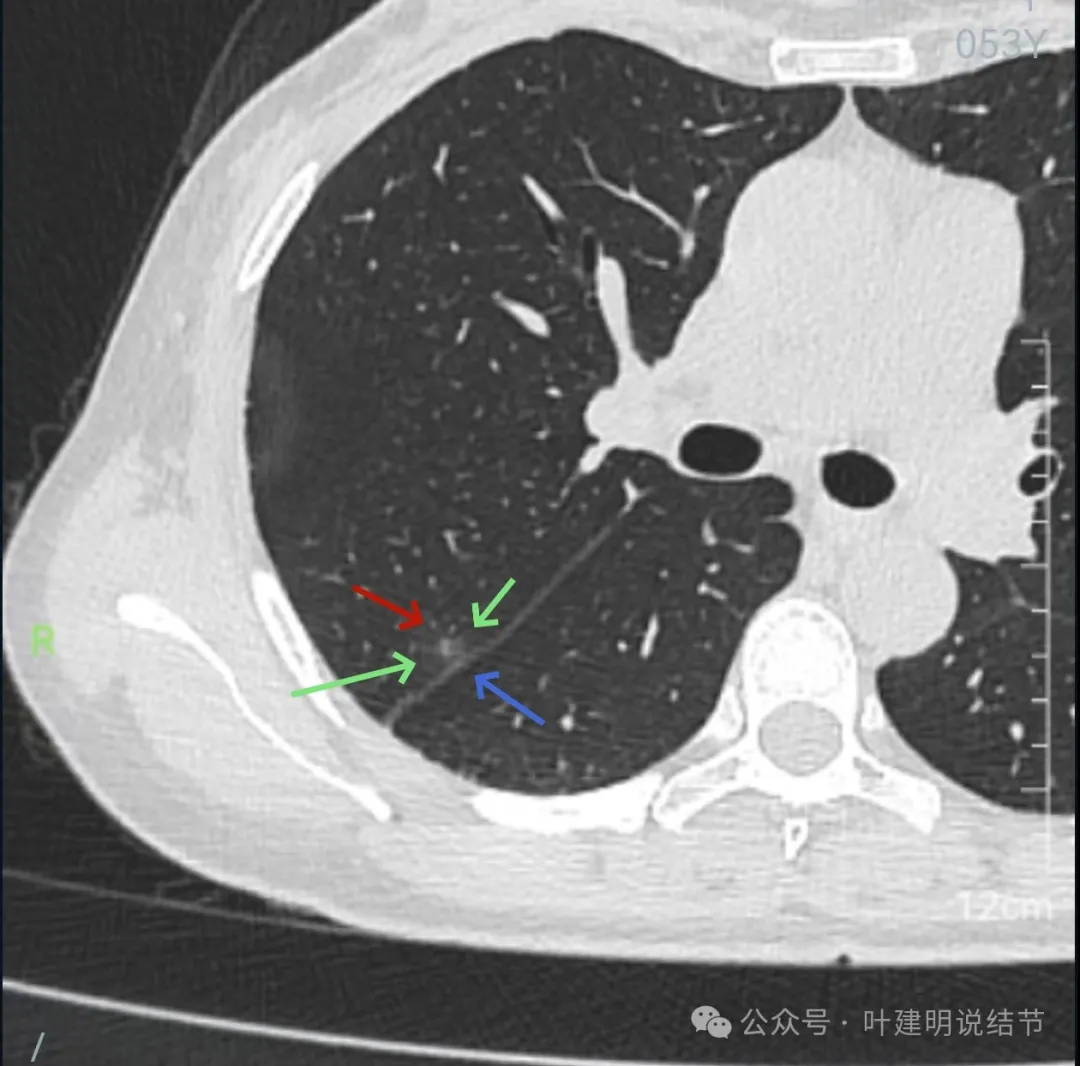

右下叶以及左下叶实性结节,缺乏膨胀性,没有收缩力,紧贴胸壁或膈肌无牵拉凹陷。

蓝色的是实性的小结节,缺乏膨胀性,两次检查都有,没有变化,考虑是良性的;红色的这些事10月份检查新增的,这两处比较明显的9月份的时候就是绿色框起来这个区域,当时是没有的。短时间内出现、多发病灶、边缘模糊、轮廓欠清,没有恶性特征,与炎性病变符合。建议查查隐球菌方面的化验,如此结果阳性,请呼吸内科或感染科处理。意见供参考!

再来看周教授认为4B类的右上后段病灶连续层面影像信息:

几乎贴着叶间裂了,仍无任何牵拉影响。

病灶密度边缘部分也不均,离叶间裂近而没有影响。

上图病灶已经贴着叶间裂,但仍显示是平直的,没有任何牵拉影响。

矢状位上看,病灶虽整体轮廓较清,但瘤肺边界显模糊,整体不致密。

冠状位上看病灶有实性成分,实性成分缺乏收缩力,外围是淡磨玻璃成分,瘤肺边界欠清,贴着叶裂没有影响。

从连续层面以及影像细节上看,这个病灶就不可能是恶性的!短期内出现,混合密度而瘤肺边界不清,整体缺乏收缩力也无膨胀性,灶内实性成分不致密且磨玻璃成分过淡,灶内血管有异常增粗与密度过高,又是两肺多发病灶。这所有的表现与病情发展都与感染性病变契合,周围淡磨就是炎症水肿的关系,血管异常就是管壁有炎症的关系,多发就是感染(致病因素)影响两肺的关系。怎么可能是恶性?